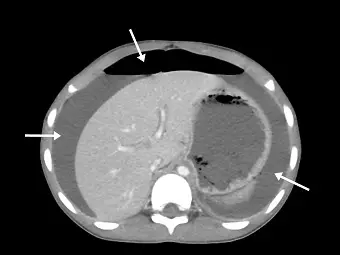

患者誤食雞骨頭,兩天後腹痛難耐,注射對比劑後的電腦斷層影像顯示異常處(如下圖箭號所示),最適當的診斷為何?

這是一張仰臥位(supine position)的腹部水平切面(axial view)電腦斷層影像,影像層面位於肝臟與胃部:

- 上方白色箭號:指向腹壁下方、肝臟與胃部前方一個巨大的半月形極低密度(黑色,呈現空氣密度)區域。因為病患平躺,腹腔內的游離空氣會往最高處(前腹壁下方)聚集,這是非常典型的**氣腹(pneumoperitoneum / free air)**徵象。

- 左側與右側白色箭號:分別指向肝臟周圍(perihepatic space)以及脾臟/胃部周圍(perisplenic space)的低密度液體堆積。這代表腹腔內有游離液體(free fluid / ascites),在腸胃道穿孔的情境下,這些液體通常是外漏的消化液、食物殘渣或發炎所產生的滲出液。